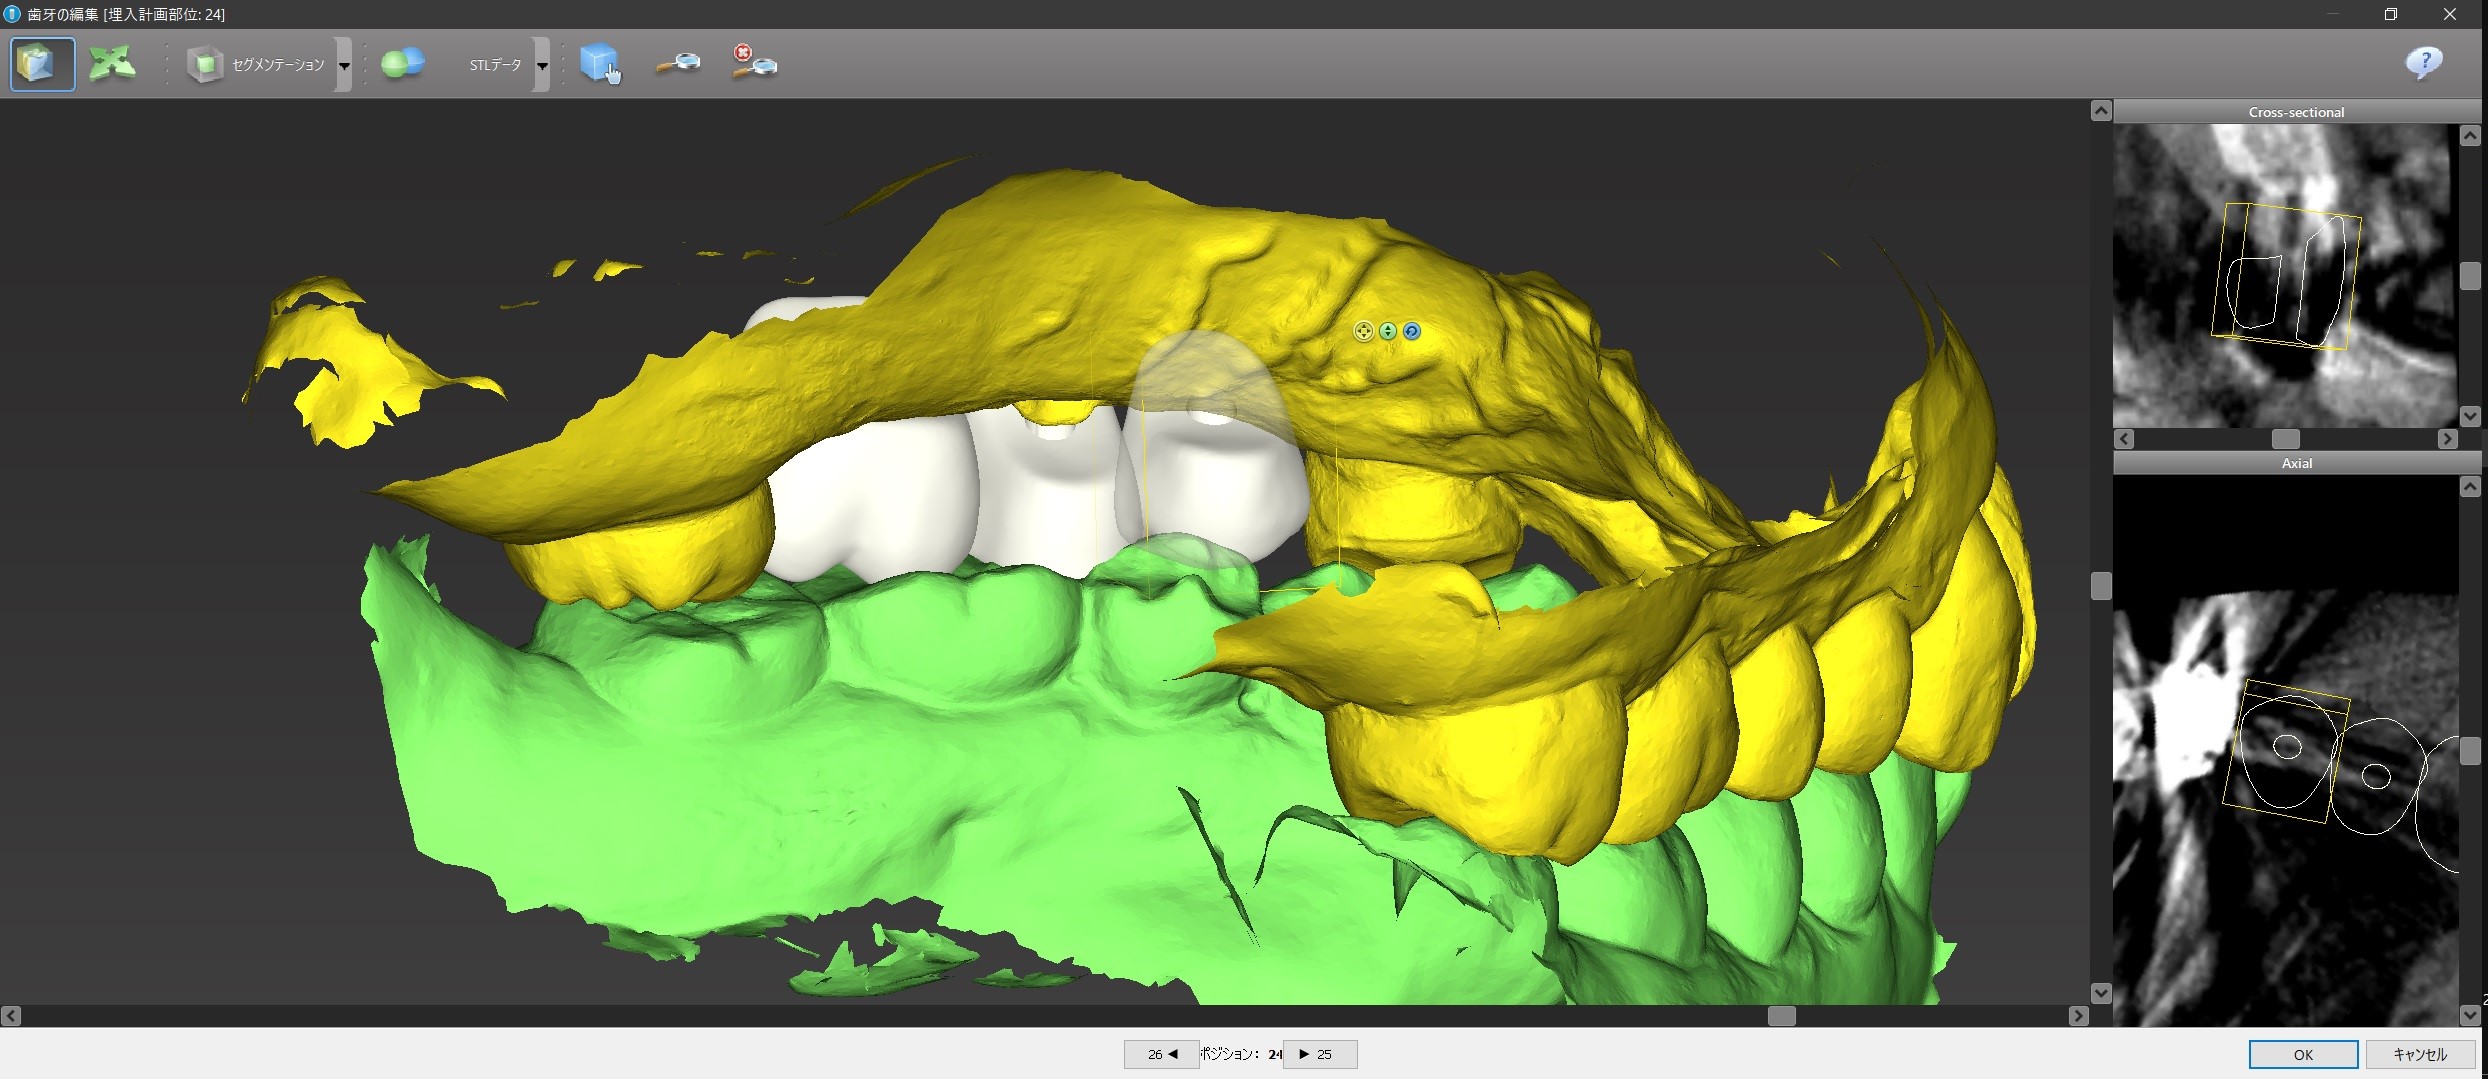

1本下の歯が内側に傾いているために、上下で噛み合わないヴァーチャル・ティースがあるのが分かります。

これが噛むようにするには、1本だけかなり内側にインプラント上の歯(「上部構造」といいます)を置かなければならならず、歯並びもおかしくなってしまうので、とりあえずこのヴァーチャル・ティースに合わせてインプラントをシュミレーションしてみます。

問題点とその解決方法を検討して、患者さんにコンピューター画面を見せながら説明して希望をお聞きします。

① #24がその前の天然歯に当たって、そもそもこの位置に入れられない。

② 前述のように#24上部構造が下の歯と咬まない。ちゃんと咬むようにするためには矯正治療が必要になる。

③ #24のインプラントと上部構造との間に角度を付けるか、もしくはGBR(骨を増やす、作る処置)が必要になる。

今回、④の問題は対応が優しく、#25、#26部位はインプラントを入れる条件がかなり良いため、#24にはインプラントを入れずに#25と#26にだけインプラントを入れて、それを土台としたインプラントブリッジの設計にして、#24が下と咬まないことはご了承して頂くか矯正治療をするか相談するということになります。

そして方針が決まれば、コンピューター上でシュミレーションした位置に正確にインプラントが入れられる「サージカル・ガイド」を作成することになります。